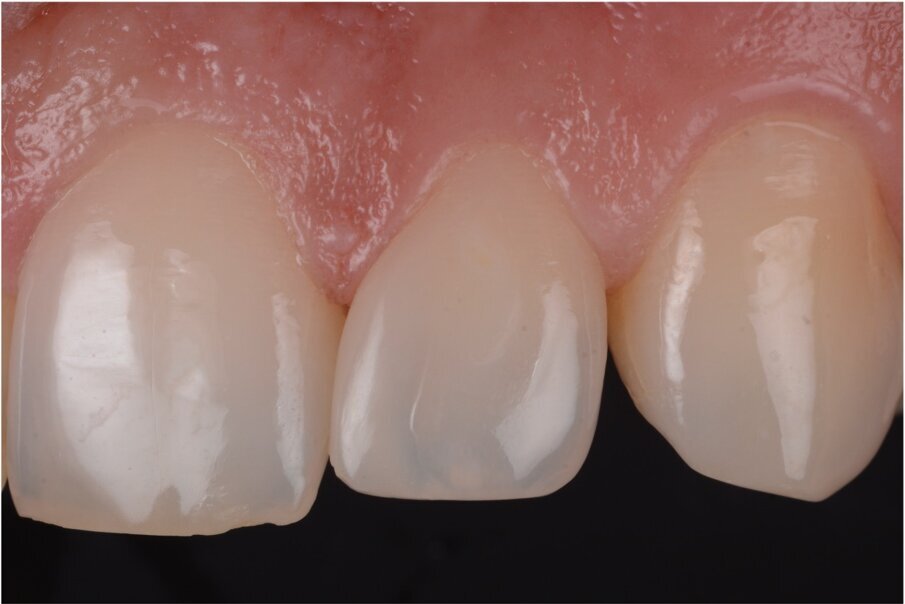

Case 3: Diastema closure, layered with dentin and enamel to match opacity and incisal fractures correction (1 hour chair time)

Case 3, Fig. 1.

Case 3, Fig. 2.

Case 3, Fig. 3.